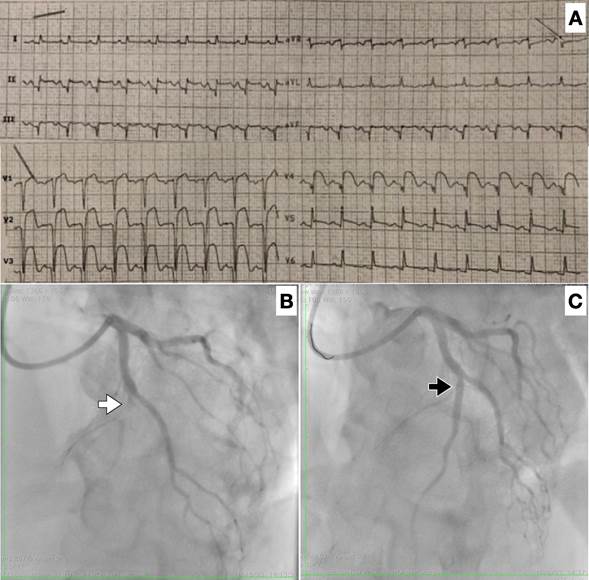

Hombre de 66 años, sin factores de riesgo cardiovascular, que consultó por ángor de 16 horas de evolución y síncope. Al examen físico se constató mala perfusión periférica, hipotensión, taquicardia, estertores crepitantes difusos y un soplo sistólico intenso con máxima auscultación a nivel paraesternal izquierdo. El electrocardiograma (Figura 1 A) evidenció qS con elevación mantenida del segmento ST en las derivaciones V1-V6 y DII-DIII-AVF. Con planteo de infarto agudo del miocardio con elevación del segmento ST anterolateral extenso evolucionado, Killip y Kimball IV, se inició soporte inotrópico y vasopresor, y se trasladó para cineangiocoronariografía de emergencia. Esta evidenció oclusión trombótica aguda de la arteria descendente anterior en tercio medio, para lo cual se realizó angioplastia con implante de dos stents liberadores de everolimus (Figura 1 B y C).

Figura 1 A.  Electrocardiograma al ingreso. B. CACG que evidencia oclusión de ADA media (flecha blanca). C. Angioplastia exitosa de ADA con implante de stent (flecha negra).